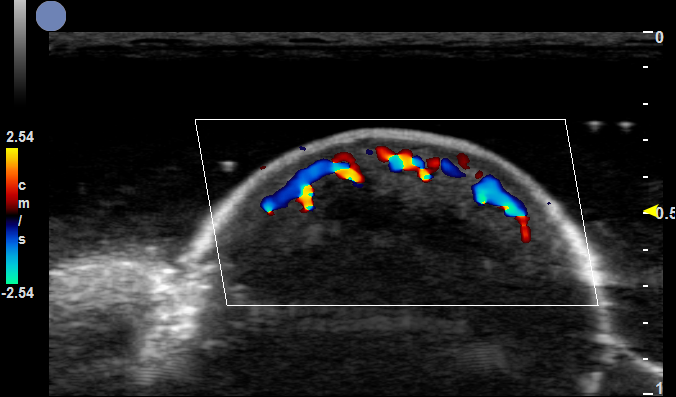

①临床皮瓣移植研究:超高频超声用于穿支皮瓣手术和毛细血管穿支的可视化,精确观察毛细血管在皮下和真皮层内的走向,精确标记浅筋膜穿支的位置,以优化皮瓣设计方向。

可用于薄和超薄穿支皮瓣术前监测和定位、选定超薄穿支皮瓣用于重建极薄软组织缺损(特别是手指、手、脚、脚趾、包皮和外耳道)

穿支血管

血流速度